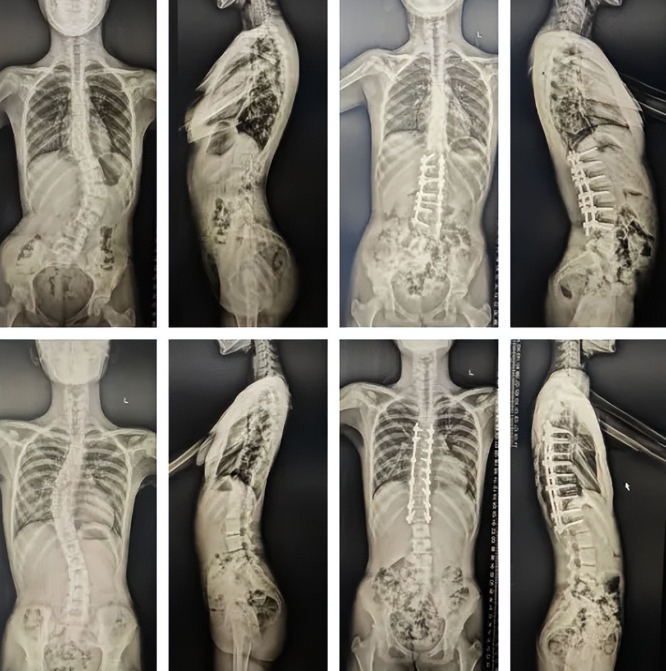

两位患者术前、术后